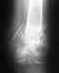

Re: Перелом б/берцовой и малой берцовой кости в н/3 со смещением отломков

По поводу перелома костей голени ничего предпринимать не нужно, все приемлемо. В сроке 2 мес. нужно посмотреть снимки и решить по нагрузке и необходимости удаления винта вверху.

Касательно проблем с коленным суставом - в любом случае сейчас надо восстановить амплитуду движений, лучше с участием методиста, хотя можно и самому.

После возврата к обычным нагрузкам - если появятся проблемы с коленом, то обратиться к специалисту по артроскопии. Сейчас обсуждать все возможные варианты проблем и их решений не имеет смысла.